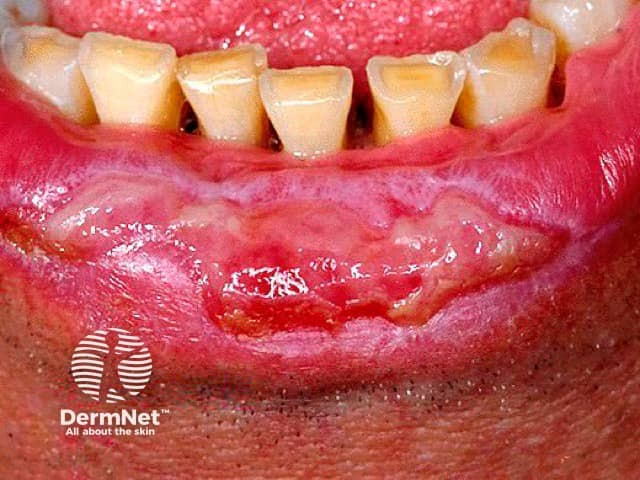

Aphthous Ulcer

口瘡性潰瘍

CD8+ T cell 破壞上皮 30y↓, 非角化上皮

• 40% 患者有家族史

• 中間黃,外紅暈

• Minor type

• 最常見,80%

• buccal and labial mucosae

• φ: 3-10mm

• 7-14d 癒合

• 熱癢痛, 7-14 天消失

• Major type

• 較深

• φ: 1-3 cm

• 2-6w 癒合

• Herpetiform

• 多發,且頻繁復發的 Minor